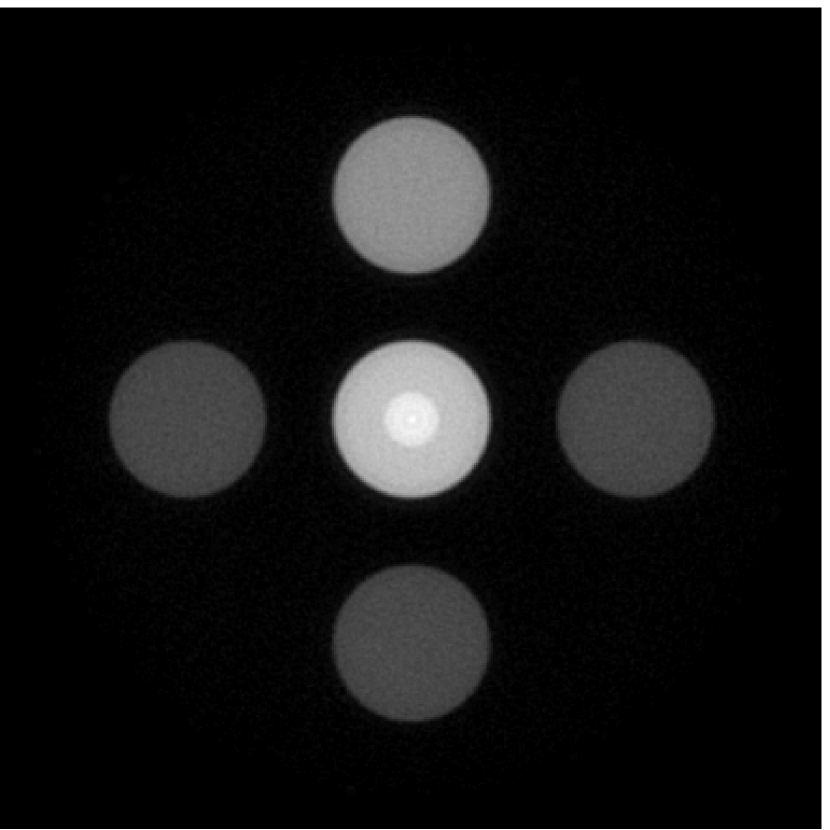

V-B1 Mitigation of artifacts and distortions caused by an inaccurate EIR

Figure 7(a) reveals that use of the inaccurate EIR in the conventional iterative method created strong artifacts and distortions. Figures 7(b) confirms that the artifacts and distortions were significantly mitigated when the VP method was employed. Image profiles for both cases are shown in Figures 7(c). The overall accuracy of the recovered EIR, shown in Figure 7(d) and 7(e), was improved, but it contained spurious oscillations.